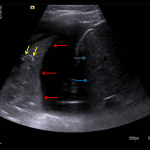

Indication: Pneumonia, assess pleural effusions

- Moderate to large bilateral pleural effusions without internal complexity

- Consolidated, liver-like appearance of both lungs with multiple air bronchograms

Pneumonia with parapneumonic effusions

Bilateral airspace consolidation with air bronchograms, consistent with pneumonia. Adjacent moderate to large, simple appearing parapneumonic effusions.